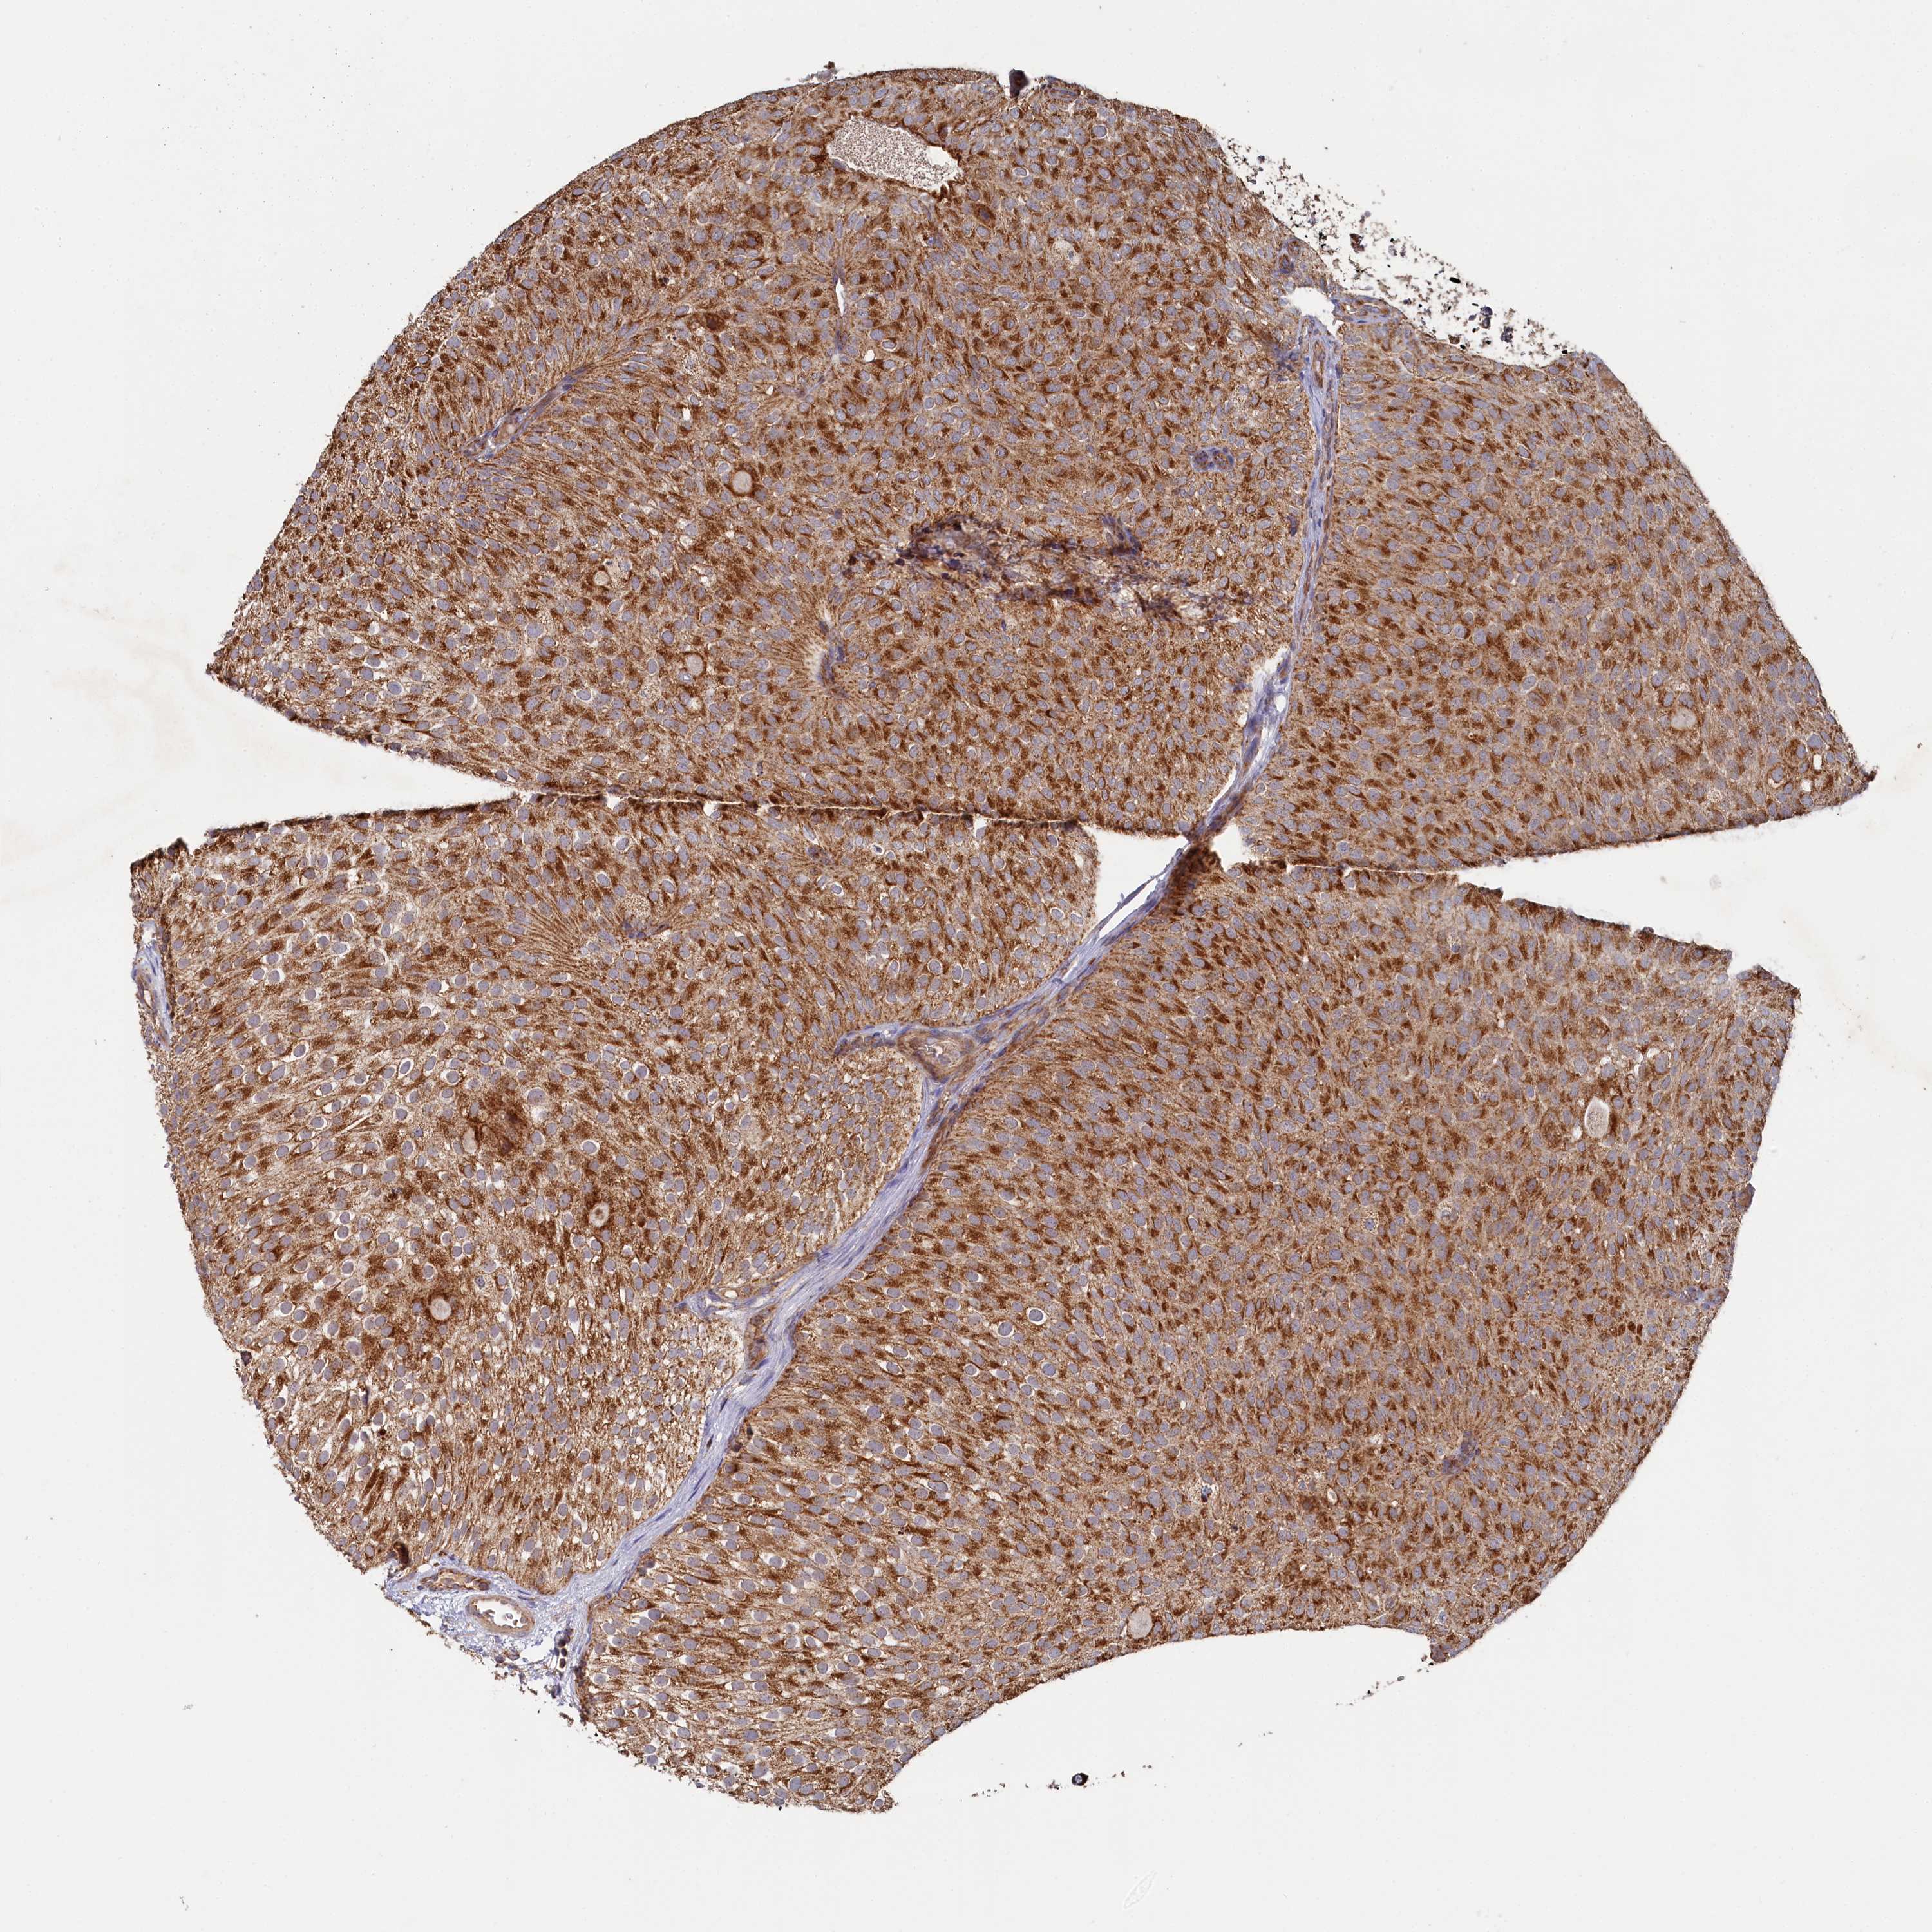

UROTHELIAL CANCER - Protein expressioni

A mouse-over function shows sample information and annotation data. Click on an image to view it in a full screen mode. Samples can be filtered based on level of antibody staining by selecting one or several of the following categories: high, medium, low and not detected. The assay and annotation is described here.

Note that samples used for immunohistochemistry by the Human Protein Atlas do not correspond to samples in the TCGA dataset.

Antibody stainingi

Antibody staining in the annotated cell types in the current human tissue is reported as not detected, low, medium, or high, based on conventional immunohistochemistry profiling in selected tissues. This score is based on the combination of the staining intensity and fraction of stained cells.

Each image is clickable and will lead to virtual microscopy that enables deeper exploration of all samples and also displays staining intensity scores, fraction scores and subcellular localization as well as patient and tissue information for each sample.

Antibody HPA039965

Staining

High

Medium

Low

Not detected

Intensity

Strong

Moderate

Weak

Negative

Quantity

>75%

75%-25%

<25%

None

Location

Nuclear

Cytoplasmic/membranous

Cytoplasmic/membranous,nuclear

Urothelial carcinoma, High grade

Urothelial carcinoma, Low grade